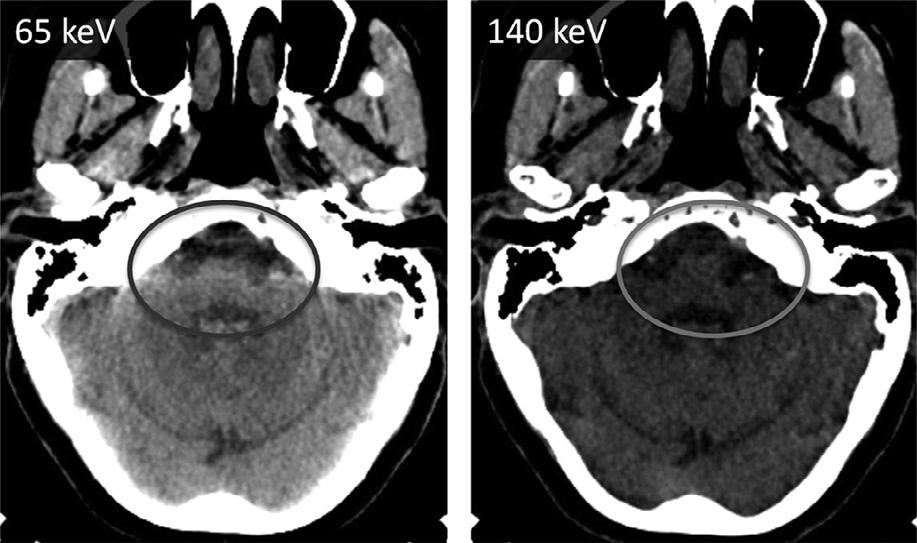

AdvancesinCTneuroimaginghaveparalleled advancesincomputerprocessingspeedandinefficiency ofimagereconstructionalgorithms.Mostrecently,iterativereconstructiontechniques – thefirstgenuinely novelCTimage-processingdevelopmentsinceHounsfield’sfilteredbackprojectionmethodology(forwhich hewasawardedtheNobelPrizein1979) – havemade possiblehighspatialresolution,reducednoise,very lowradiationdoseCTscanning(Rapalinoetal.,2012). Theimprovedscanningspeed, z-directioncoverage,spatialresolution,contrastresolution,andlowradiation dosecapabilityofpresent-dayCTscannershavealso facilitateddual-energyimaging,which – forthefirst time,likeMRI – hasallowedtissue-specificcharacterizationofintracranialpathology,includingdedicatedCT imagingthatcanreliablydistinguishcalcium,iodine,fat, water,andhemorrhage(Guptaetal.,2010).Virtual monochromaticdual-energyCTimagesalsohavethe potentialtohelpreducetheposteriorfossabeamhardeningartifactcausedbydenseboneattheskullbase (Pomerantzetal.,2013).

Fig.1.17. Dual-energyvirtualmonochromaticimagesofacontrast-enhancedbrainatthreedifferentenergylevels:50keV(top right),65keV(bottomleft),and130keV(bottomright).Withdual-energycomputedtomography,virtualmonochromaticreconstructionatlowerkeVlevelsimprovesintravascularenhancementandcontrast-to-noiseratioastheX-rayphotonenergymoves closertothe k-edgeofiodine(33.2keV).Ascanbeseen,theattenuationwiththevesseljumpsfrom169HUto1156HUwhenwe movefrom130keVto50keV.Withthischange,thebrainparenchymaonlygoesfrom18HUto45HU.Thisfactcanbeusedto drasticallycutdowntheamountofcontrastthatisadministered,withobviousbenefitsintermsofrenalhealth.

Thesametrick,infact,canbeusedwithanysubstancewithhighdensitythatcausesbeamhardening. Forexample,thevisualizationoftheposteriorfossacontents,especiallythebrainstem,isseverelydegradedby beam-hardeningartifactarisingfromthepetrousridges

laterallyandtheclivusanteriorly.Asshownin Figure1.20,onecanconsiderablyreducethisartifact usingthevirtualmonochromaticimages.